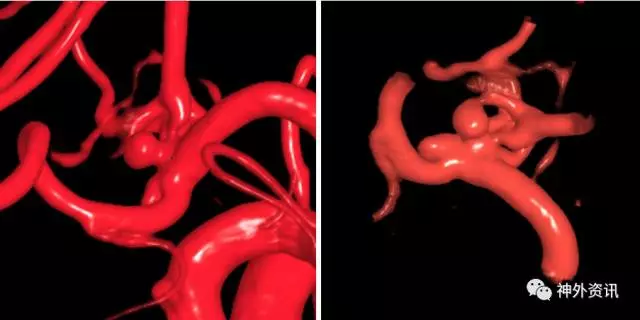

(3D重建:动脉瘤形态极不规则,远/近端血管迂曲严重伴狭窄)

(3D血管融合:左侧额颞顶部巨大AVM,大小约10.4*6.7*5.7cm)

1例右侧额叶AVM伴右侧额叶血肿

(挑战:终末血管供血,超选距离遥远,途经血管迂曲,选择使用Envoy DA)